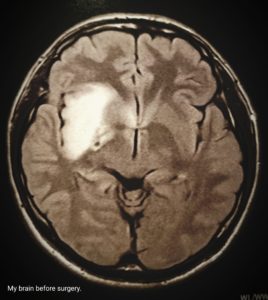

記憶 : 腫瘍摘出、開頭手術後あからさまに感じる脳の記憶力の違い……

記憶 : Obvious difference in brain memory after tumor removal or craniotomy……

Memory : Obvious difference in brain memory after tumor removal or craniotomy……